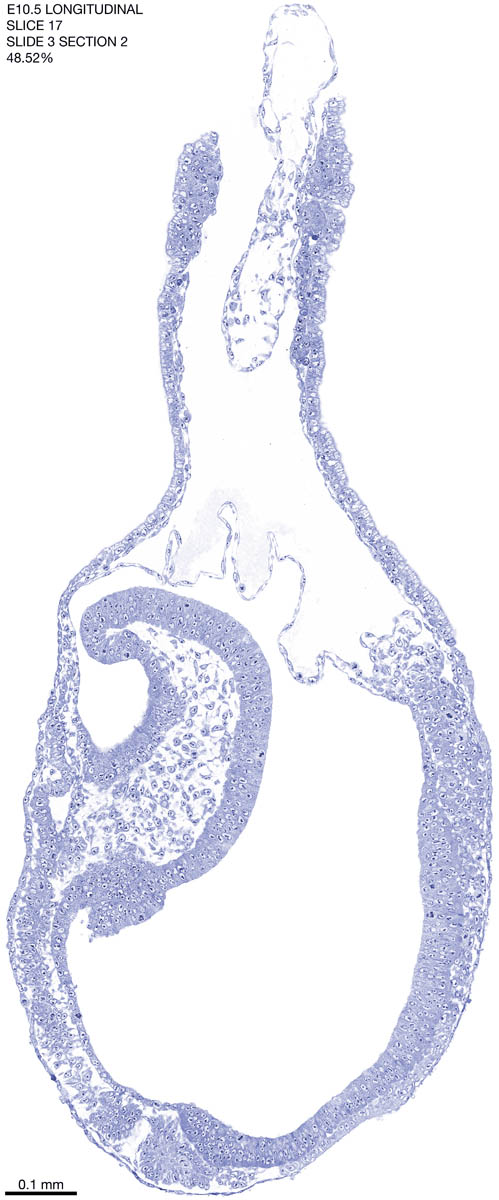

E10.5 Longitudianal Archive This page contains jpg files of ALL SLICES (each 3µm thick) that were scanned of the E10.5 longitudinally cut specimen. Download: Large | High Res Download: Large | High Res Download: Large | High Res Download: Large | High Res Download: Large | High Res Download: Large | High Res Download: Large | High Res Download: Large | High Res Download: Large | High Res Download: Large | High Res Download: Large | High Res Download: Large | High Res Download: Large | High Res Download: Large | High Res Download: Large | High Res Download: Large | High Res Download: Large | High Res Download: Large | High Res Download: Large | High Res Download: Large | High Res Download: Large | High Res Download: Large | High Res Download: Large | High Res Download: Large | High Res Download: Large | High Res Download: Large | High Res Download: Large | High Res Download: Large | High Res Download: Large | High Res Download: Large | High Res Download: Large | High Res Download: Large | High Res Download: Large | High Res Download: Large | High Res Download: Large | High Res Download: Large | High Res Download: Large | High Res Download: Large | High Res Download: Large | High Res Download: Large | High Res Download: Large | High Res Download: Large | High Res Download: Large | High Res Download: Large | High Res Download: Large | High Res Download: Large | High Res Download: Large | High Res Download: Large | High Res Download: Large | High Res Download: Large | High Res Download: Large | High Res Download: Large | High Res Download: Large | High Res Download: Large | High Res Download: Large | High Res Download: Large | High Res Download: Large | High Res Download: Large | High Res